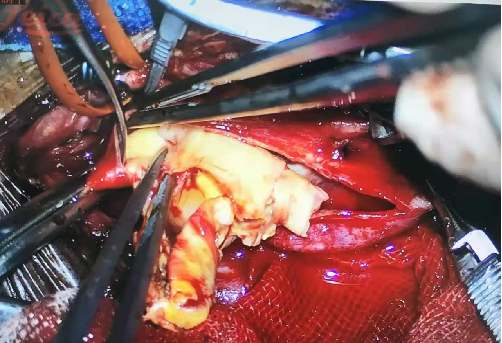

2021-4-27 全麻下行颈内动脉内膜剥脱术

术后无新发神经功能障碍,右上肢远端肌力升至4级。MRI未见出血、新发梗死;MRA示左侧颈内动脉管径基本恢复正常;PWI示左侧大脑半球灌注增加